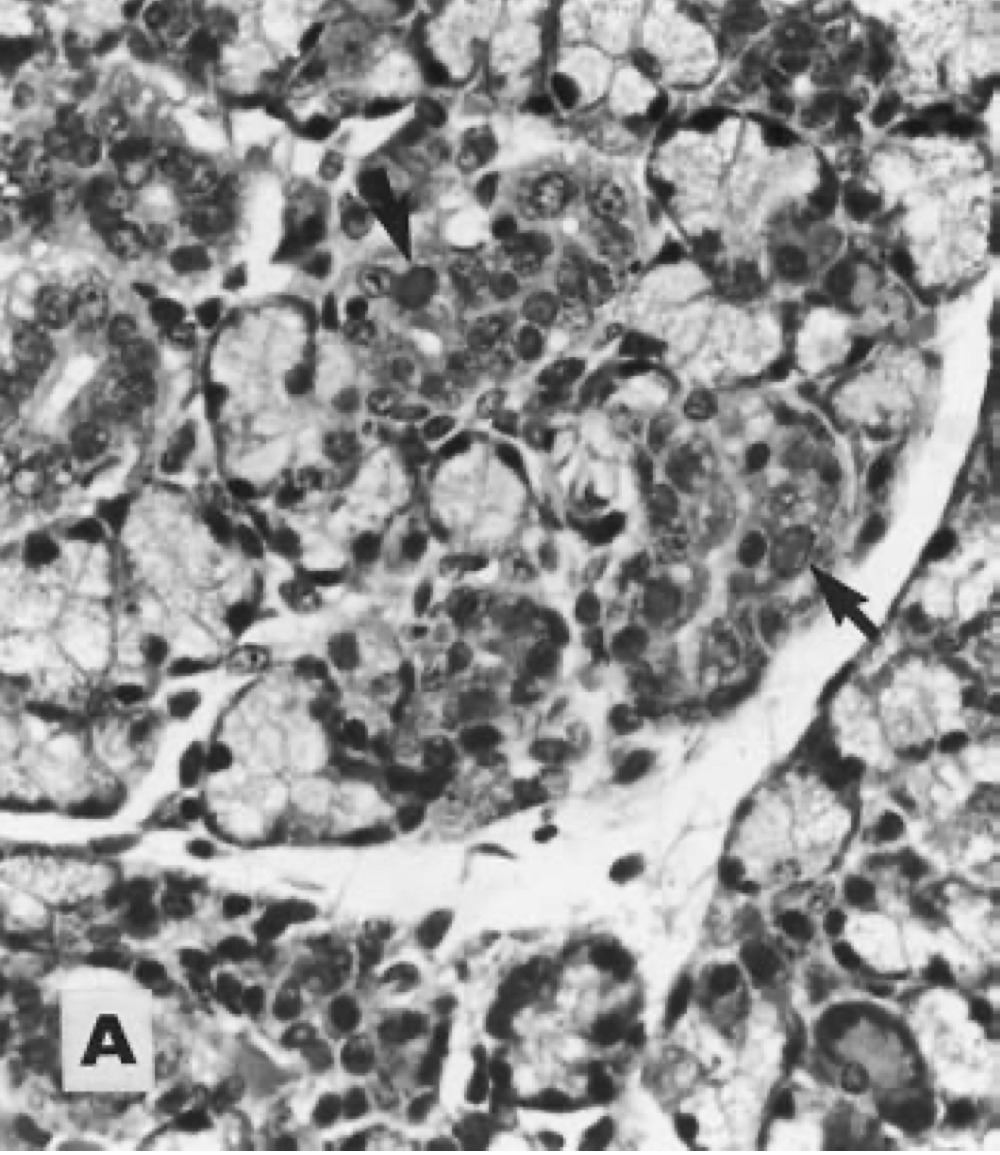

77.由一隻消瘦、毛髮粗糙的天竺鼠的唾液腺組織切片中發現下圖病變,最可能的致病原為下列何者?

Guinea pig with cytomegalovirus infection